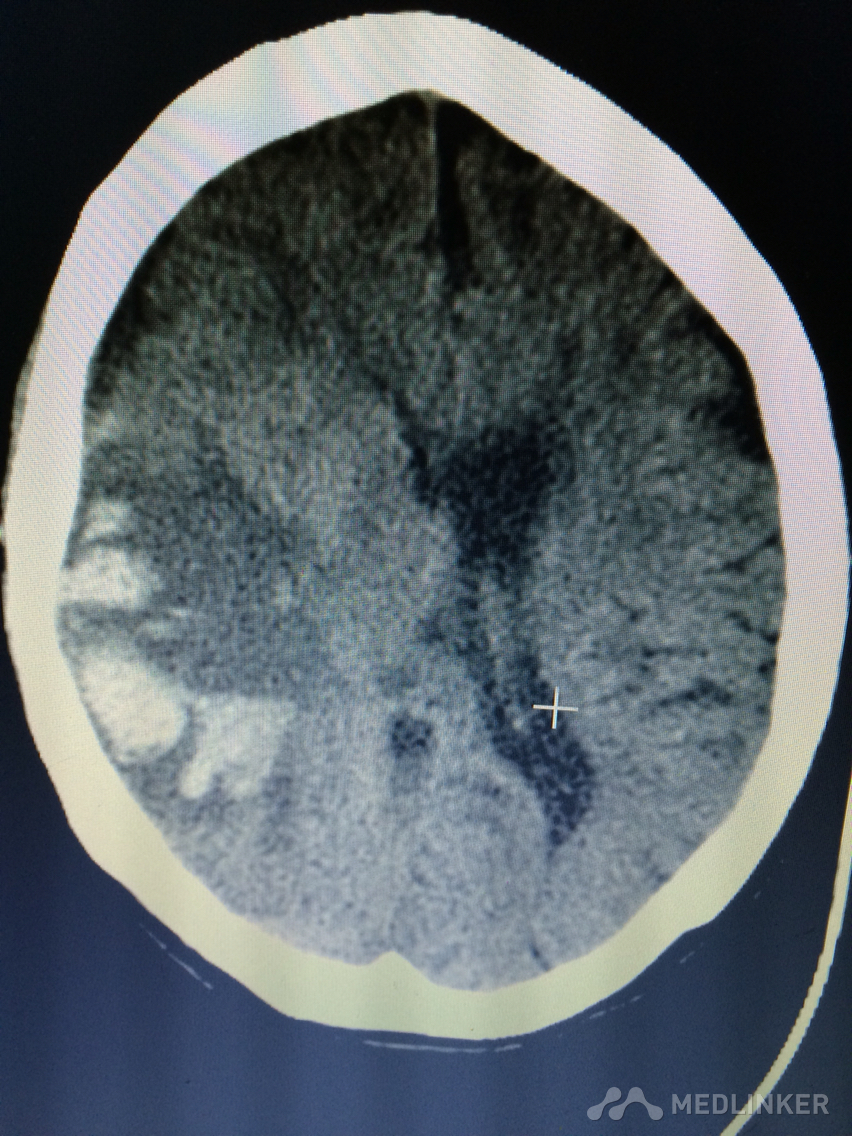

下面的CT考虑?

1天前,患者睡醒后出现反应迟钝,认知功能障碍,左侧肢体乏力。 既往无高血压病史,近期无外伤史。